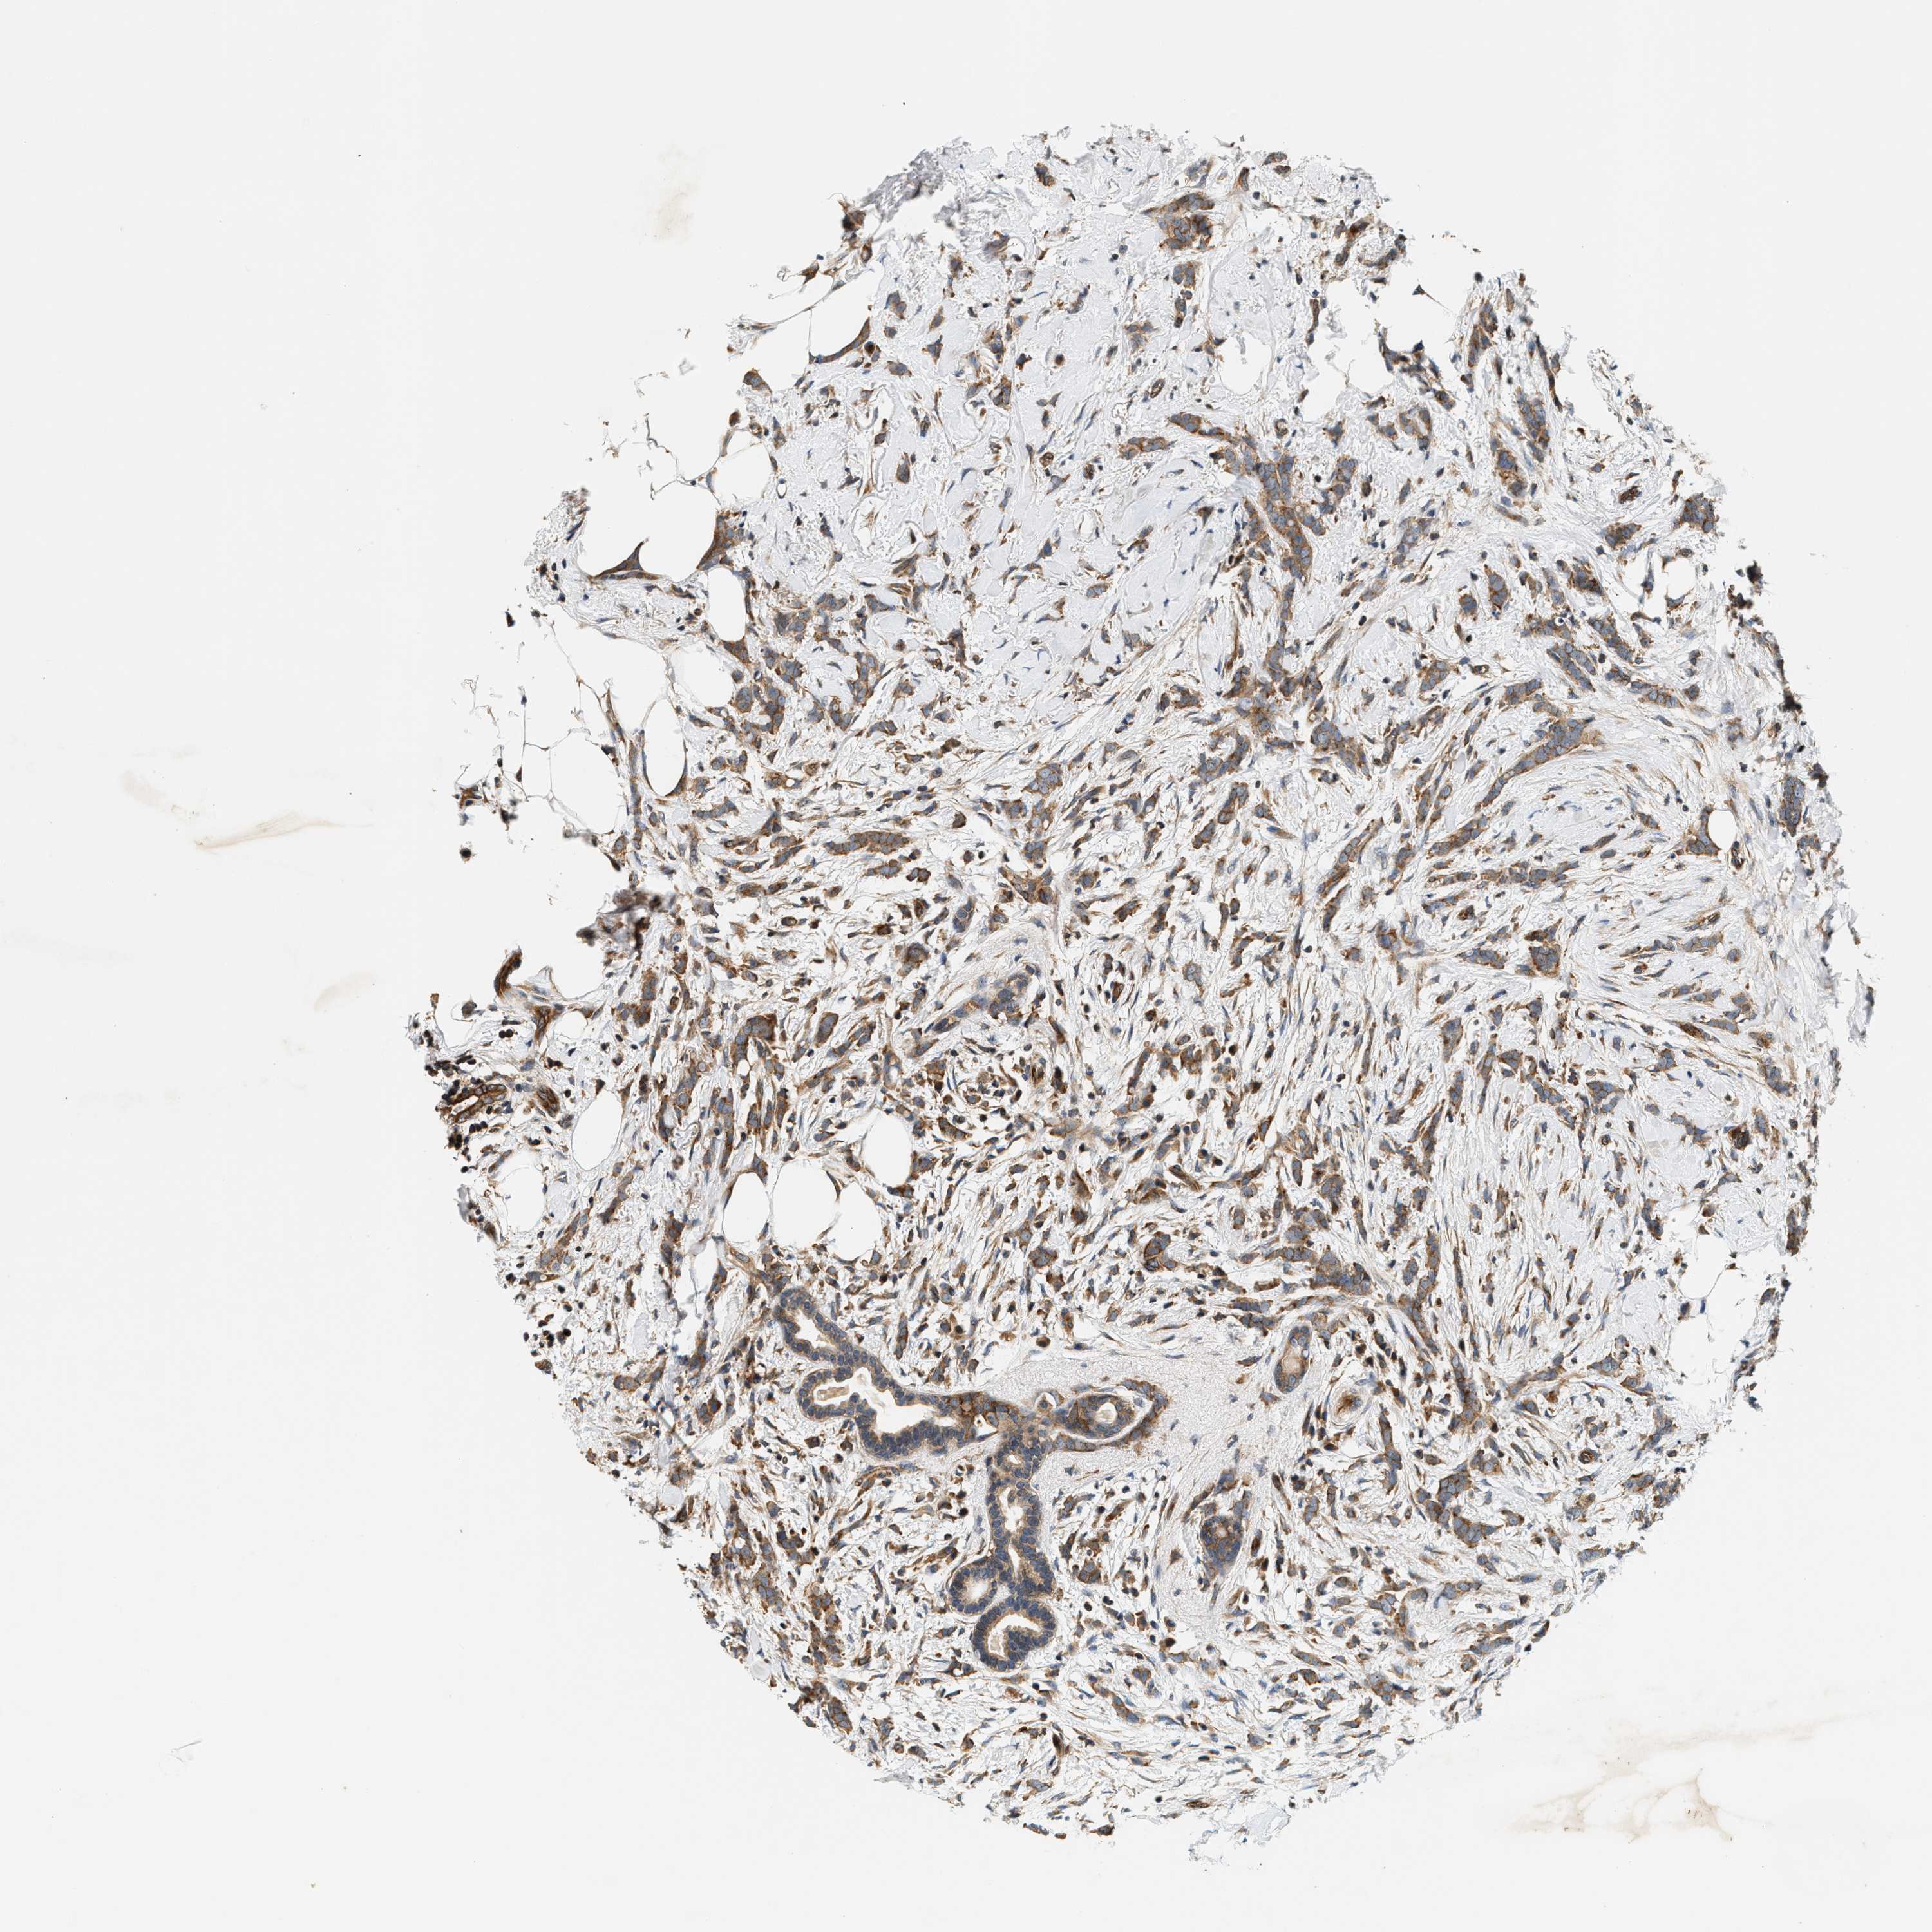

CANCER BREAST CANCER Show tissue menu

BRCA TCGA BRCA VALIDATION PROTEIN EXPRESSION